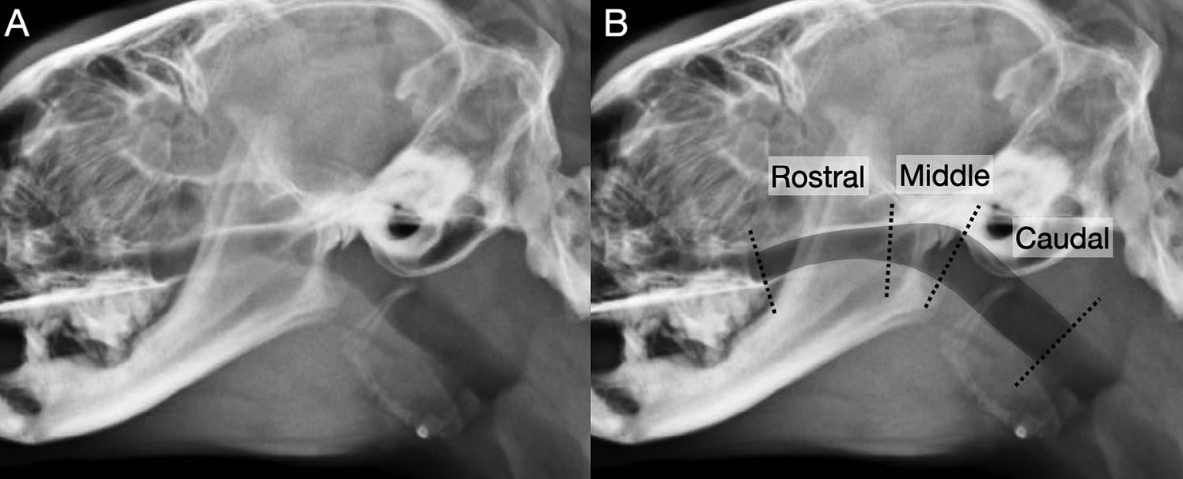

이번 연구는 다기관, 후향적, 단면 연구로 설계되었습니다. 코골이 증상으로 내원하여 측면 두부 방사선 검사와 비강내시경 검사를 모두 받은 고양이 52마리의 의료 기록을 분석했습니다. 이 고양이들은 내시경 검사 결과에 따라 비인두 협착증으로 확진된 그룹(NPS 그룹, 21마리)과, 코골이 증상은 있지만 협착은 없었던 그룹(ND 그룹, 31마리)으로 나뉘었습니다. 이후 두 명의 영상의학 전문의가 진단 정보를 모르는 상태에서 방사선 사진을 검토하여 협착의 유무, 위치, 형태 등을 평가했습니다.

- 착의 형태: 방사선학적으로 비인두 협착증이 확인된 사례 중, 대부분은 넓은 부위에 걸친 광범위한(broad) 형태의 협착(18/21마리)으로 관찰되었으며, 일부는 얇은 막 형태의 막성(membranous) 협착(3/21마리)으로 나타났습니다.

- 이적인 연구개 형태: ‘구부러진(bent)’ 형태의 연구개가 비인두 협착증 그룹의 19%(4/21마리)에서 관찰되었으며, 이는 협착이 없는 그룹에서는 전혀 발견되지 않은 특이적인 소견이었습니다.